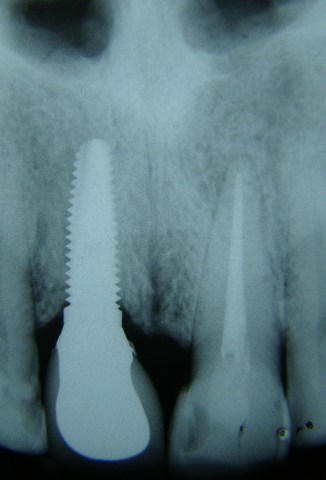

Paciente apresentava uma ausência do elemento 46 (primeiro molar inferior) e queixava-se d...